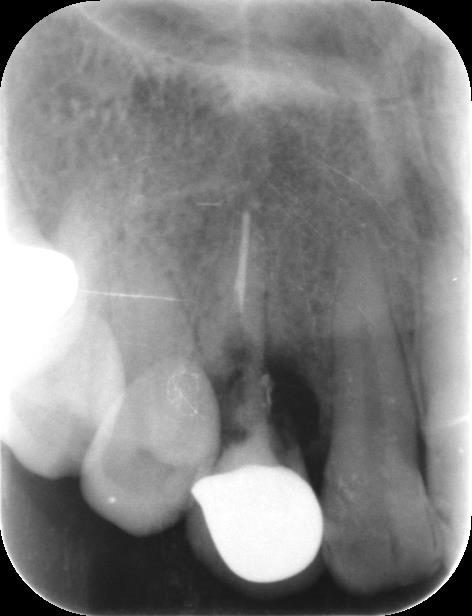

症例12

30代 男性 前歯が折れてしまった。

術前 レントゲン

| 主訴 | 前歯の差し歯が折れてしまい、腫れて痛みがある。できるだけ隣の歯を傷つけずに治したい。 |

|---|---|

| 年代・性別 | 30代 男性 |

| 治療部位 | 上顎左側 1 |

| 治療費用 | インプラント手術料 300,000円 |

| 手術回数 | 1回 |

| 治療期間 | 6ヶ月 |

| 手術時間 | 90分 |

| 治療回数 | 4回 |